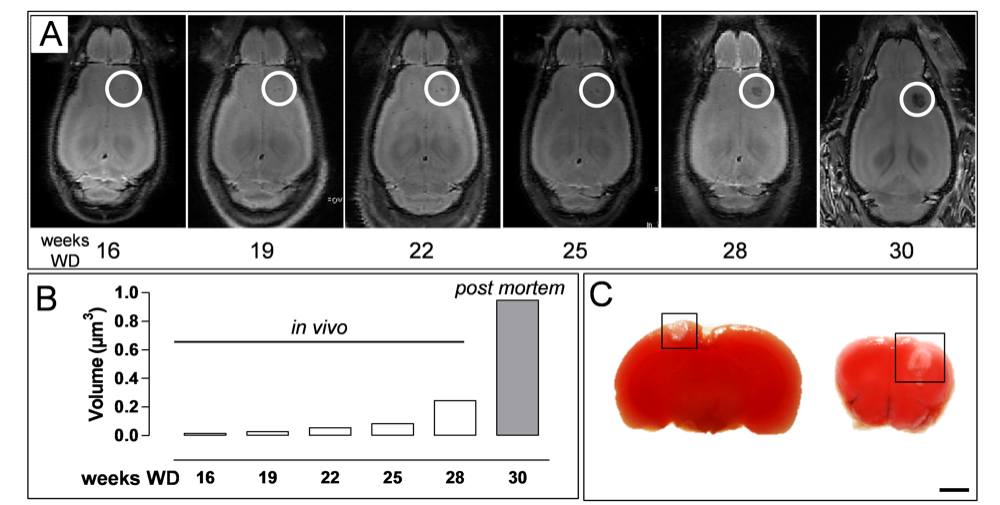

Chapter 4 Figure 5Xanthomas increase in size over time and do not induce brain hypoxia. (A) Longitudinal MRI study of the brain of an ApoE-/-Fbn1C1039G+/- mouse on WD for up to 30 weeks. Lesions were detected after 16 weeks on WD and increased exponentially in size over time (R2=0.98). (B) Quantification of xanthoma growth in the brain of mouse in (A). Weeks 16-28 on WD in vivo and high resolution post mortem MRI at 30 weeks on WD. (C) Two examples of a TTC stain of brains of ApoE-/-Fbn1C1039G+/- mice showing a xanthoma (boxed area) in the neocortex. Hypoxia was absent in the proximity of the xanthomas. Scale bar=200µm.